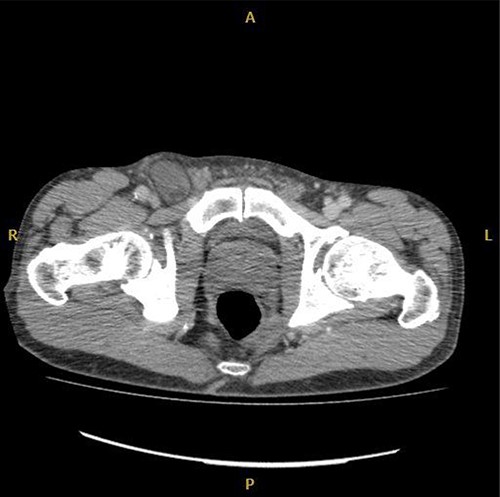

Computed tomography (CT) was reported as demonstrating an inguinal hernia containing fat and possibly the vermiform appendix (Figs 1 and 2). There was no conclusive evidence of appendicitis.

The patient was taken to theatre later that day for exploration via a modified McEvedy’s high approach. This demonstrated a hernia sac originating posterior to the inguinal ligament, emerging medial to the femoral vessels. A femoral hernia was diagnosed and exploration of the hernia sac demonstrating the vermiform appendix with necrosis of the distal segment. Appendicectomy was completed and primary suture repair used to repair the defect to the femoral canal.